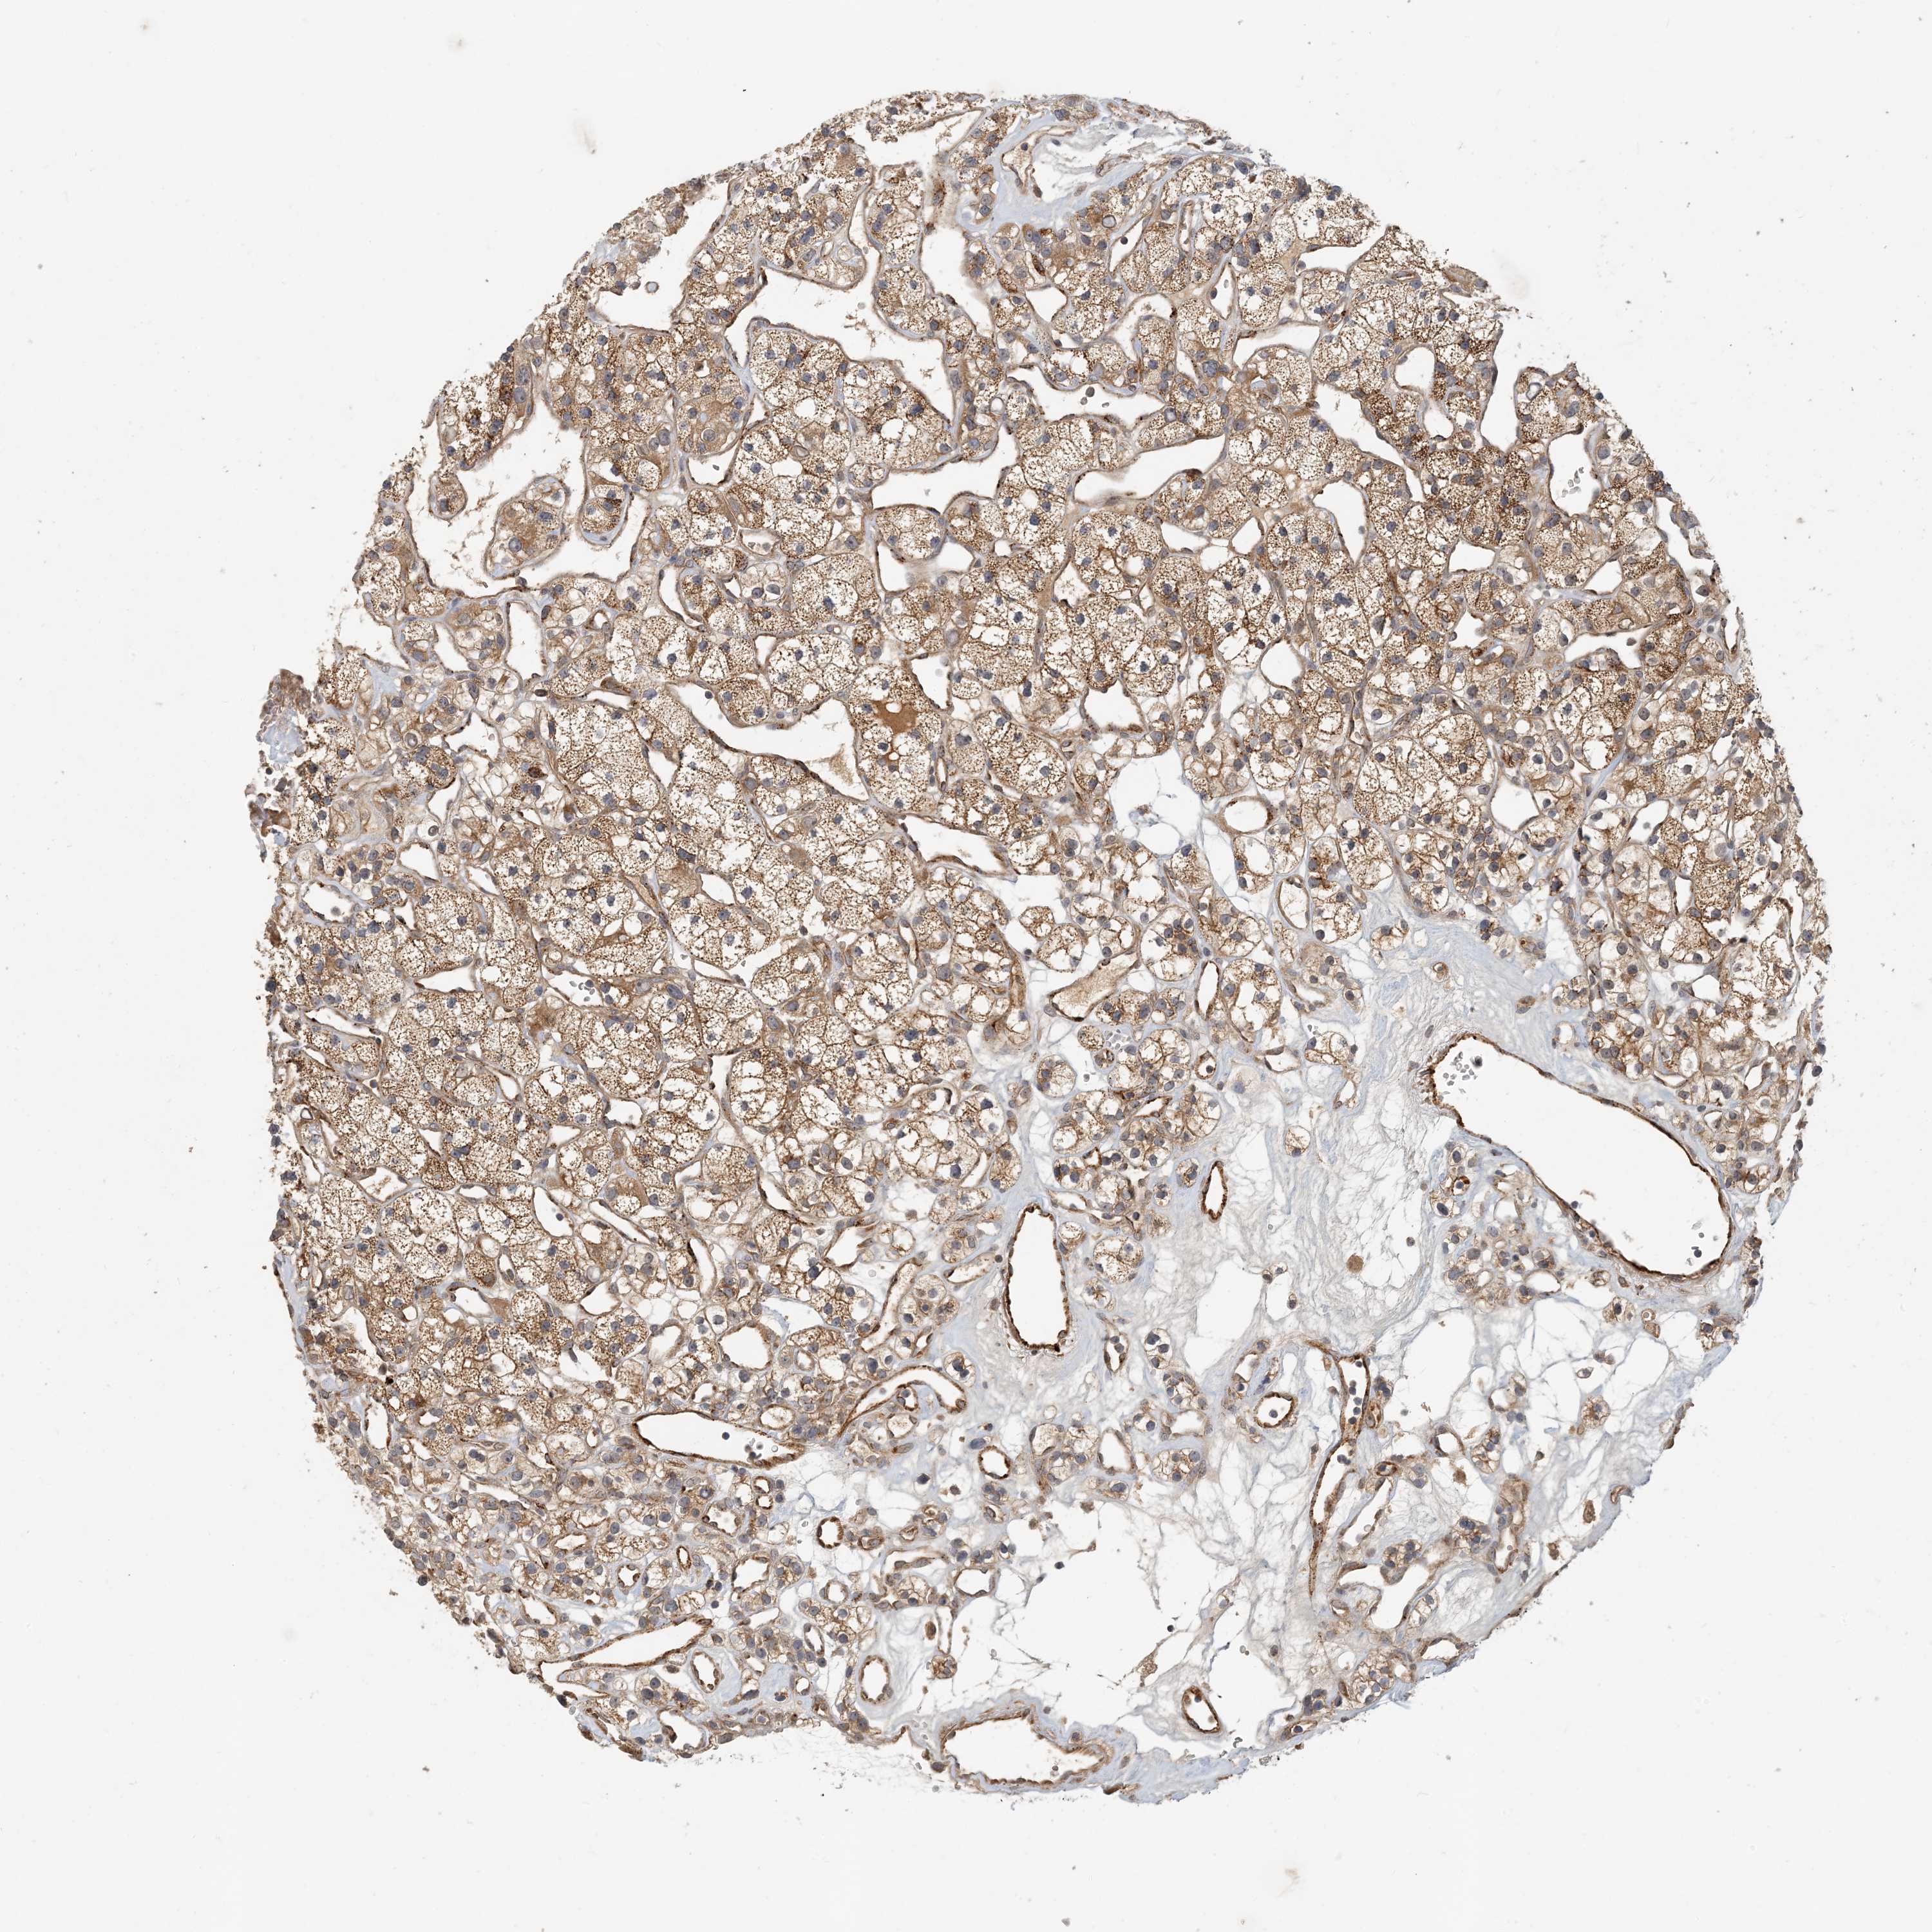

TCGA RNA samplesi

RNA-seq data is reported as average FPKM (number Fragments Per Kilobase of exon per Million reads), generated by the The Cancer Genome Atlas (TCGA) .

Normal distribution across the dataset is visualized with box plots, shown as median and 25th and 75th percentiles. Points are displayed as outliers if they are above or below 1.5 times the interquartile range. FPKM values of the individual samples are presented next to the box plot.

Average pTPM 2.2